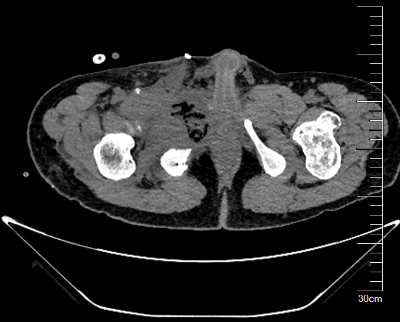

我院骨科王伟东副主任接诊后详细询问了患者疾病发展过程,并为患者做了全身体格检查,仔细查阅了患者的检查报告,综合各方面信息后,诊断患者患有“先天性多发骨软骨瘤病”,并且右耻骨上支的骨软骨瘤已经恶变为继发性软骨肉瘤。目前患者远处脏器尚未出现转移,右耻骨病灶周围解剖屏障尚完整,王主任建议患者手术治疗。

图片 2.png图片 3.png

术前CT